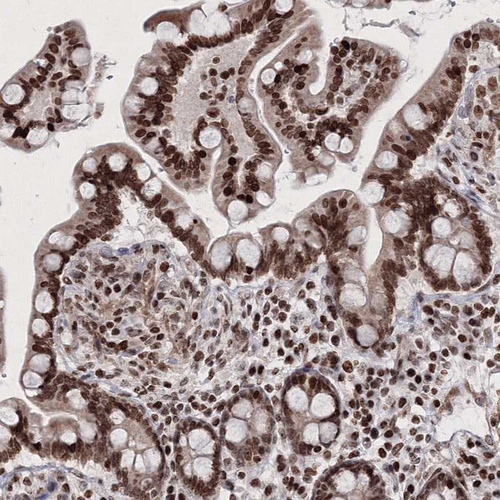

Immunohistochemical staining of human cerebral cortex shows strong nuclear positivity in neurons.